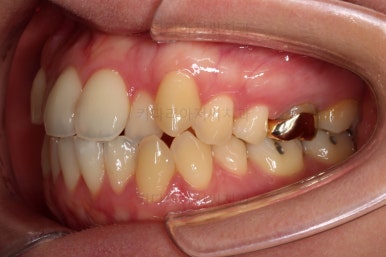

초진 시, 입안의 모습입니다.

좌측 송곳니가 덧니처럼 튀어나가 있고, 송곳니 옆의 작은 억므니가 안으로 쏙 들어가서 덧니 느낌이 더 강조되어 보이네요.

위아래 앞니가 긴밀하게 겹침이 없는 약간의 개방교합(오픈바이트, Openbite) 경향이 보입니다.

웃거나 말할 때 드러나는 치열이 삐뚤어서 심미적으로 좋지 못하고요.

옆모습에서 약간의 돌출감이 있으나 힘을 줘서 다물만큼 부자연스러운 양상은 아니여서 돌출에 관해서는 환자분의 취향에 맡기기로 했습니다.